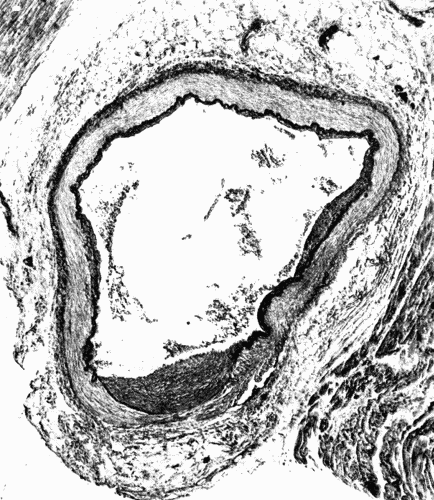

Fig. 1.—Cross section of a large artery showing the division into the three coats; intima,

media, adventitia. The intima is a thin line composed of endothelial cells. The

wavy elastic lamina is well seen. The thick middle coat is composed of muscle fibers

and fibroelastic tissue. The loose tissue on the outer (lower portion of cut) side of the

media is the adventitia. (Microphotograph, highly magnified.) Fig. 1.—Cross section of a large artery showing the division into the three coats; intima, media, adventitia. The intima is a thin line composed of endothelial cells. The wavy elastic lamina is well seen. The thick middle coat is composed of muscle fibers and fibroelastic tissue. The loose tissue on the outer (lower portion of cut) side of the media is the adventitia. (Microphotograph, highly magnified.)

The whole vascular system, including the heart, has an endothelial lining, which may constitute a distinct inner coat, the tunica intima, or may be without coverings, as in the case of the capillaries. The intima (Fig. 1) consists typically of endothelium, reinforced by a variable amount of fibroelastic tissue, in which the elastic fibers predominate. The tunica media is composed of intermingled bundles of elastic tissue, smooth muscle fibers, and some fibrous tissue. The adventitia or outer coat is exceedingly tough. It is[28] usually thinner than the media, and is composed of fibroelastic tissue. This division into three coats is, however, somewhat arbitrary, as in the larger arteries particularly it is difficult to discover any distinct separation into layers.